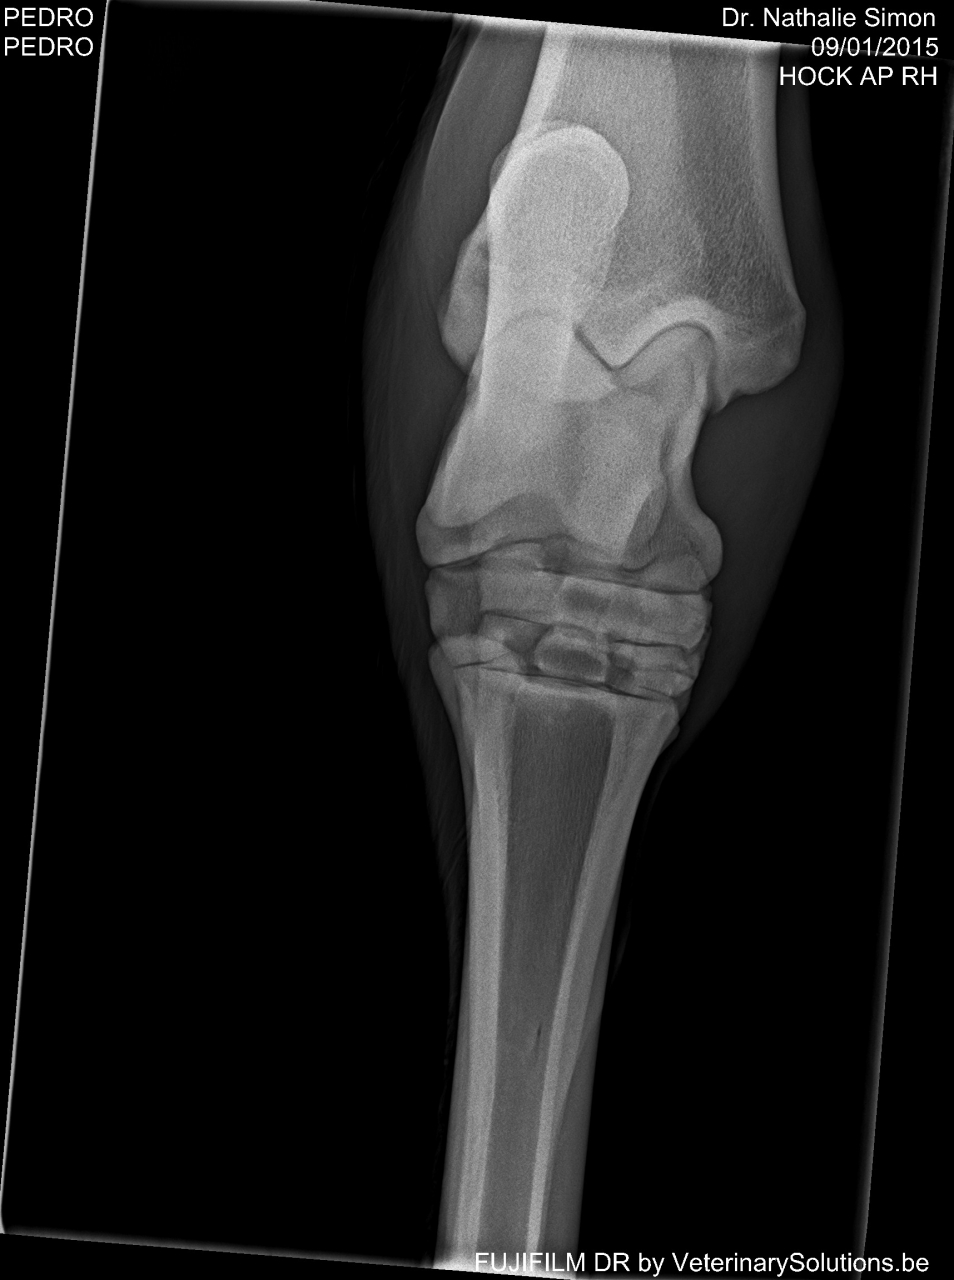

DéconnectéDire merci | Bonsoir à tous, il y a un mois d'ici mon cheval à fait un grosse chute et suite à cette chute on y a détecter un fissure au jarret.. Je souhaiterai savoir si quelqu'un a déjà vécu cela Merci d'avance et bonne soirée à vous tous !(la photo que je vous met de la radio est la seule ou on peu "voir" la fissure) ![]() |

DéconnectéDire merci | Bonjour ha c'est vraiment gentil pour la jument, en tout cas vous êtes quelqu'un de fort psychologiquement car moi j'ai déjà du mal alors qu'il n'a qu'une petite fissure :/ en tout cas merci pour le partage de votre expérience mais pouvez-vous me dire on se trouve la fracture de votre jument ? moi elle se trouve là (entourée en rouge ) |

DéconnectéDire merci | ![]() |